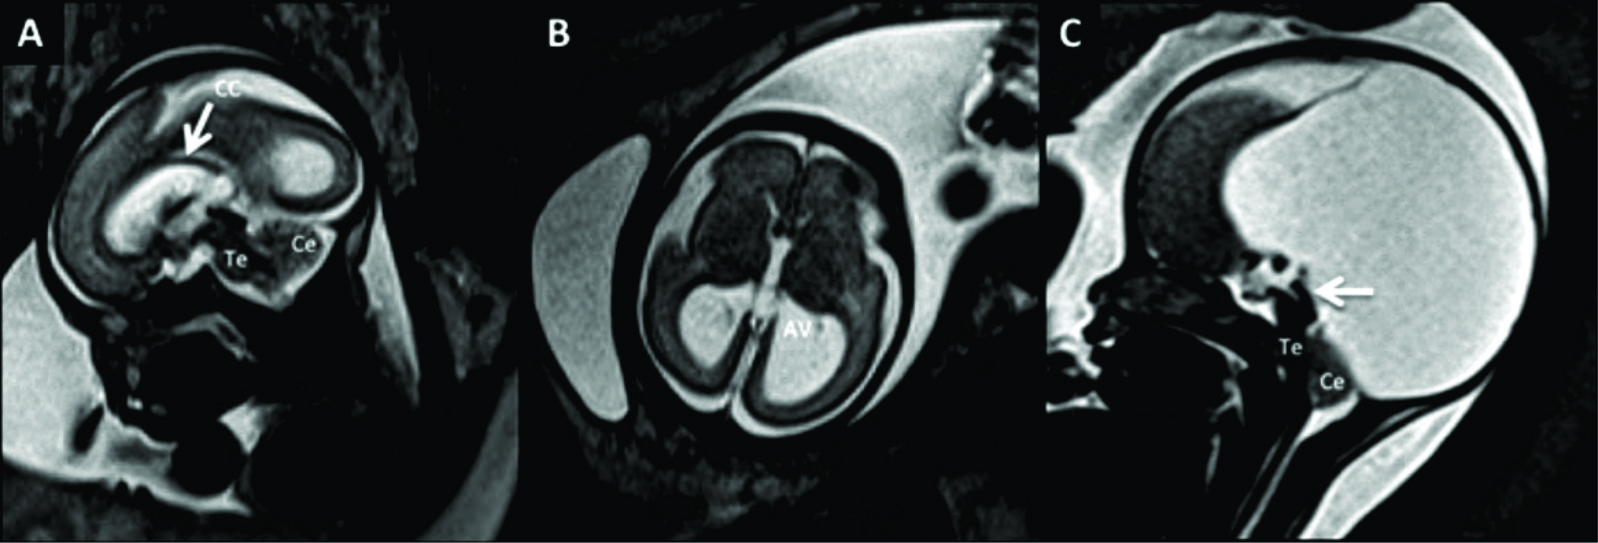

Figura 1

RM Fetal Normal (Edad Gestacional: 27 semanas).

Corte sagital en línea media (A) y corte axial a nivel bi-talámico (B) de cerebro fetal normal en la semana 27 (secuencia rápida T2). En la imagen de línea media se identifica claramente el cuerpo calloso (CC) y la cisura calcarina (è) así como también las estructuras de la fosa posterior con un desarrollo acorde.

En el plano axial se identifica la línea media y la región ganglio-basal con anatomía normal y un patrón gírico acorde a la edad gestacional con un esbozo de cisura silviana (CS).

Los diferentes sectores del sistema ventricular se identifican claramente: ventrículos laterales (VL), 3er ventrículo (situado entre ambos tálamos (T)) y IV ventrículo (situado entre el cerebelo (Ce) y tronco encefálico (Te)).

Figura 2

RM Fetal Normal (Edad Gestacional: 32 semanas).

Imágenes multi-planares de cerebro fetal normal con 32 semanas de edad gestacional donde el patrón gírico cortical ya se asemeja al del recién nacido. En el corte sagital de línea media (A) se identifica la cisura calcarina (CCal) y el surco pericalloso (SPC) rodeando a la comisura homónima (CC).

También se evalúa de forma precisa el tronco encefálico (Te) y cerebelo (Ce).

En el corte coronal (B) se evalúa de forma precisa el cerebelo (Ce) con sus 2 hemisferios y el vermis inferior (Vi).

En la imagen axial a nivel de fosa posterior (C) se evalúan las estructuras de fosa posterior, junto con el vermis (V) y el IV ventrículo en su localización habitual (è).

También se visualiza claramente la porción proximal de la cisura de Sylvio (CS).

Finalmente en el corte axial supra-tentorial (D) se visualiza claramente el patrón gírico bien desarrollado así como la región gangliobasal y el tálamo (T) así como el cavum septum pellucidum (CSL) habitual en el desarrollo.